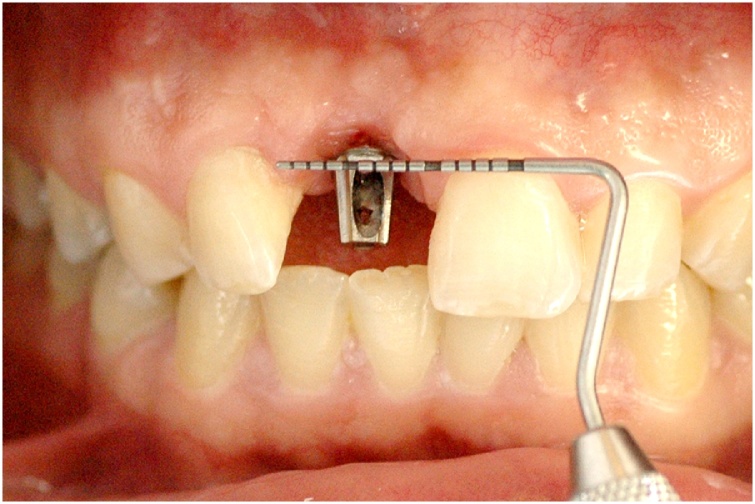

This manuscript was constructed in compliance with consensus-based surgical case report guidelines (SCARE) [9]. W. S. S. P., 29-year-old male patient, nonsmoker, nondrinker, not taking any medication, and with no relevant family history, with an implant-supported crown in central incisor #11 fabricated 8 months before, was dissatisfied with the final esthetic outcome (Fig. 1). In his dental history, the patient reported having undergone the surgical procedure for placement of osseointegrated implant. The prosthetic crown was placed 6 months after healing. Gingival retraction was observed after 8 months. Clinical examination revealed a screw-retained prosthesis through the incisal surface (Fig. 2), covered with photoactivated composite resin, stained over time by coloring agents. The gingiva was vertically retracted in the buccal region of the crown (approximately 2 mm), when compared with the cervical region of tooth #21 (Fig. 3). Ceramic coating of the prosthetic element revealed cracks on its buccal surface, whereas on the palatal surface there was excessive wear with prosthetic exposure of the metal coping. After removal of the implant-supported crown, no abutment was observed, which was considered to be the probable cause for treatment failure.

Fig. 2.

Screw access hole through the buccal surface.

Fig. 3.

Assessment of gingival retraction in the buccal region, compared with the cervical region of tooth #21.